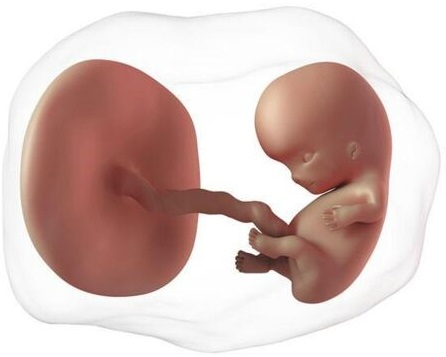

El embrión crece muy rápido, ha pasado de 4 a 14 mm en sólo una semana. Los cambios son impresionantes. En esta etapa inicia la formación de las neuronas y el cerebro ya tiene los dos hemisferios. En la cara aparecen las fosas nasales. El corazón ya tiene dos cámaras (al terminar su formación tendrá cuatro). Inicia la formación de los intestinos los cuales sobresalen a través del cordón umbilical que también está en proceso de formación.

Otro evento maravilloso es la formación de la placenta. La placenta se pone en contacto con el útero para obtener nutrientes y oxígeno. Aunque la placenta es un "órgano fetal", tiene la mitad de sus genes del padre. Para tu sistema de defensa es un tejido extraño, como un trasplante de otra persona. El sistema de defensa se regula para no rechazarla, pues las células de la placenta tienen "un permiso especial", diferente a cualquier otra célula humana, y además producen unas proteínas que se comunican con tus defensas. Con todo ello, el sistema inmunitario "reconoce" que se trata de la placenta y actúa de forma única en toda la biología: no sólo no ataca a un tejido extraño, sino que lo protege y se deja "invadir".